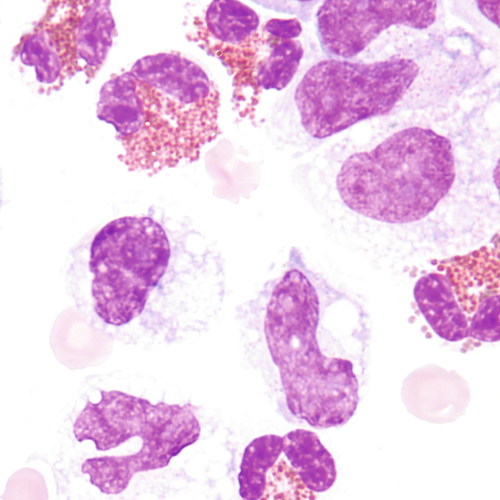

It is not always possible to distinguish malignant cells from mesothelial cells with the use of solely the light microscope. The following criteria for malignant cells may aid in this distinction.

High N:C ratio, membrane irregular

Multiple, large with irregular staining

Hyperchromatic with uneven distribution

Irregular membrane

NOTE: Smears with cells displaying one or more of the above characteristics should be referred to a qualified cytopathologist for confirmation. See Table 24–1 for a comparison of benign and malignant features. Malignant cells tend to form clumps with cytoplasmic molding. The boundaries between cells may be indistinguishable.